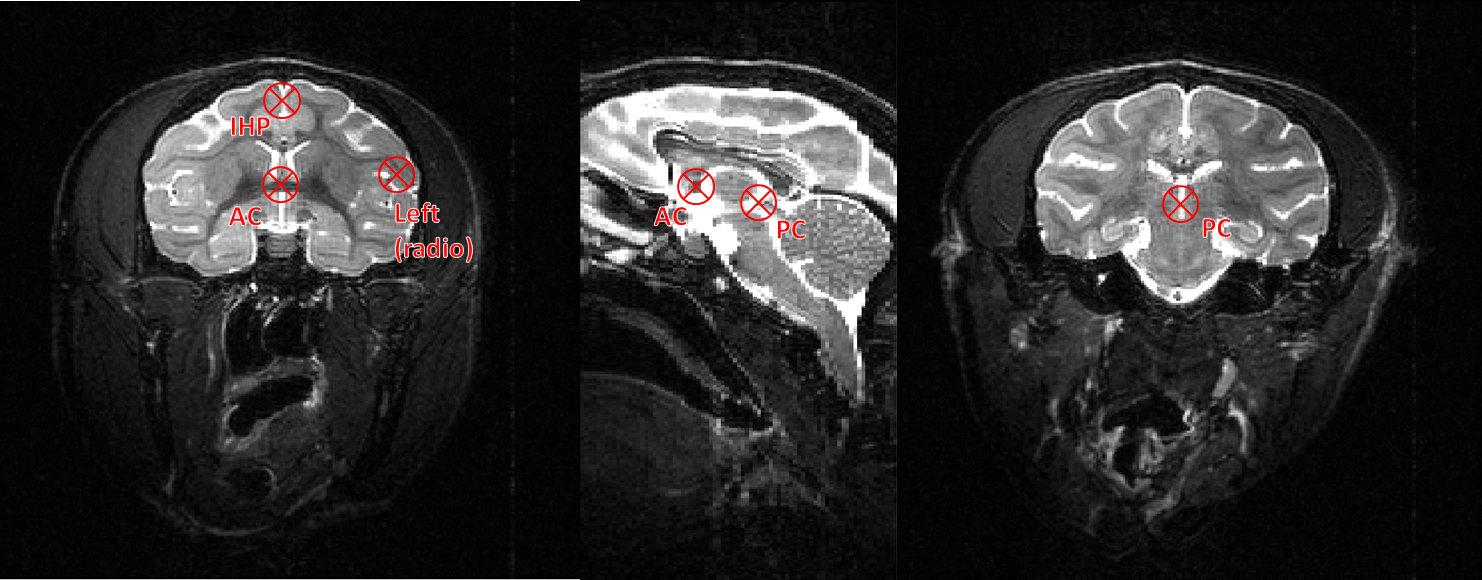

The position of points AC and PC is depicted Figure 2. The easiest way to find them is from the sagittal view: the user should find the intersection between each of these points and the interhemispheric plane. In the example image, because of the use of a stereotaxic frame, the interhemispheric plane is already aligned and both AC and PC can be selectedc from the same sagittal section. This might not always be the case though.

The interhemispheric point should be selected above the AC-PC line in order to correctly orient the volume.

If the scanner outputs image in radiological orientation, the left hemisphere point will be located, as in Figure 2, in the right side of the image. If no left hemisphere point is provided, the orientation will be kept as is. Else, the process will output the image in radiological orientation.

Figure 2. Location of AC and PC in the Macaque brain. The IHP should be selected above the AC-PC line.